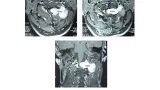

X線では骨折を認めず, 加齢による腰椎変性所見のみ.

腰椎矢状断像(左)では, 椎間板の後方への膨隆と椎間関節の肥大・黄色靱帯の肥厚によって, 縦に白く写る脊柱管が圧排されており, その中に見える神経(馬尾)がうねるようになっています(馬尾弛緩).

腰椎水平断像(右)では, 本来楕円形に見える脊柱管が圧排されて, 三角形や扁平に変形しています.

MRIでは, 第2/3, 3/4, 4/5腰椎の各椎間で脊柱管狭窄を認めました。

第5腰神経根に由来する痛みは, 殿部からふともも, すねの外側, 足の甲に放散します.

疼痛の分布から, 第4/5腰椎椎間高位での第5腰神経根障害による殿部痛と診断しました.